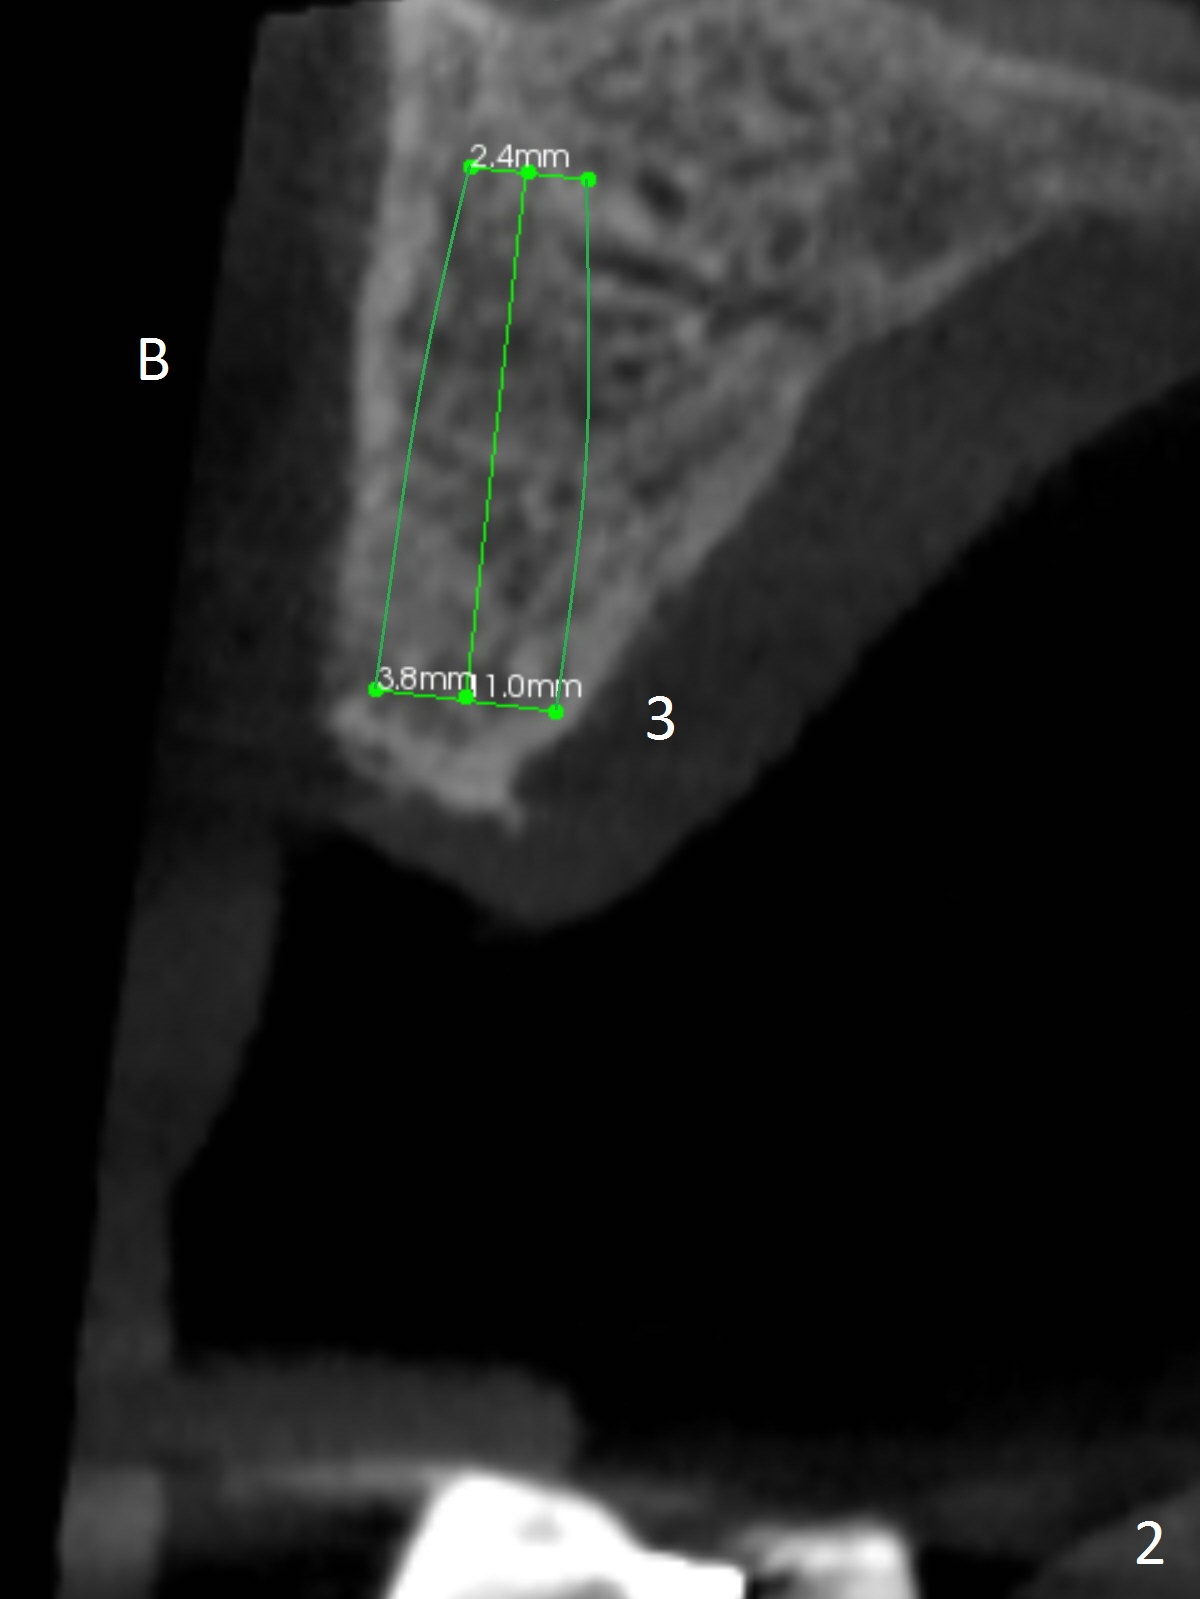

A 83-year-old woman requests lower RPD to replace #18-20 and 23-26 (Fig.1), although UR FPD supported by implants at #3 and 5 (Fig.2,3) is a better option.  For the RPD, an implant will be placed at #18 (Fig.4) or 17 (Fig.5) with ball abutment.  At #18, a shorter implant will be placed at the top of the Inferior Alveolar Canal (brown), while at #17, a longer implant will be placed buccal (B) to the canal.